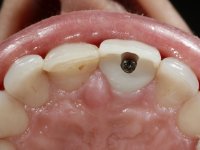

52-year-old female patient, non-smoker. He used an appointment with an implant already placed in the 1.1 site. It was provisionally rehabilitated with a composite resin crown adhered to the palatal surface of the adjacent teeth. This provisional had taken off several times in the last month, even in this first consultation it was taken off. We took advantage of this situation and verified that the “Tissue Level” implant had 2 to 3 mm of prosthetic space available. A deep bite and the inclination of the long axis of the implant posed a very difficult situation for the rehabilitator. If one chooses a abutment with a cemented crown, the height of the abutment would be minimal, with no retention or resistance. If a screwed solution is chosen, the screw access hole would emerge through the vestibular surface. It should be remembered that in 2006 the prosthetic solutions for this situation were limited to these options: 1- Screw-retained angled metal abutment for cemented crown 2 - Screw-retained angled metal abutment for transversally screw-retained crown 3 – Syn Octa metal abutment for screw-retained crown. A serious problem in this rehabilitation was guessed right from the start. The patient had a thick gingival phenotype and good oral hygiene.